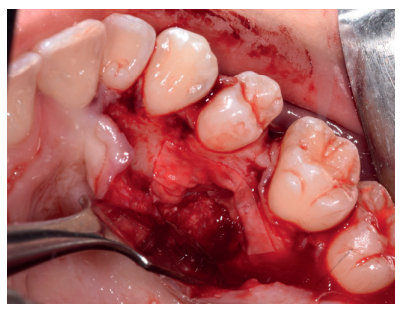

Caso clínico: se presenta un caso clínico de una mujer de 20 años, sin antecedentes médico-quirúrgicos de interés, que acudió a consulta remitida por su ortodoncista, para la extracción de un premolar maxilar retenido, en posición invertida. Tras la extracción del premolar y del tercer molar inferior retenidos, se obtuvo dentina procedente de ambos, para la regeneración ósea guiada del defecto resultante de la extracción del premolar, realizando revisiones a la semana y a los 4 meses de la intervención.

Clinical case: a clinical case of a 20-year-old woman is presented, with no interesting medical record, who went to dental clinic for removal of an inverse maxillary bicuspid retained. After maxillary bicuspid and lower third molar extractions, autogenous dentin was obtained from both teeth, to perform a guided bone regeneration of the bicuspid defect. A week and 4-month check-up were carried out.